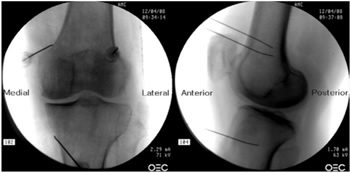

Figura 3